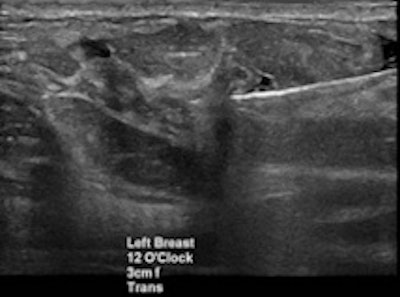

Breast cancer findings include masses, calcifications, developing asymmetry, and skin thickening, which is often imperceptible, Shaheen said. For whatever reason the patient is called back -- a finding on mammography, a clinical finding, or a patient discovering a symptom -- the diagnostic path generally begins with multimodality imaging, followed by image-guided biopsy. Then comes the critical rad-path correlation and, ultimately, assessment of cancer pathology and hormonal status before deciding on treatment, which greatly depends on the individual case.

Perhaps there are suspicious microcalcifications in a case of recurrent breast cancer. Should the patient undergo bilateral fine-needle aspiration or ultrasound-guided biopsy? Has lymph-node status been checked? Radiologists should measure not just the size of the lymph nodes but the thickness as well.